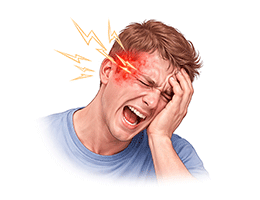

편두통 (Migraine)

군발두통 (Cluster headache)

뇌졸중 (Stroke)

뇌출혈 (ntracerebral Hemorrhage)